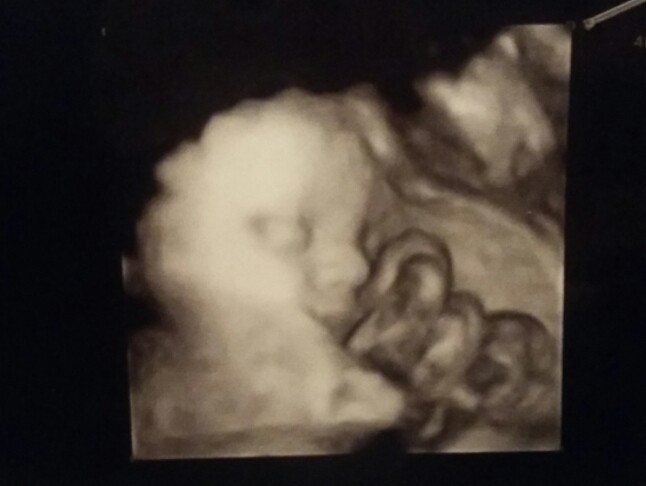

• PART_1488289337434_mms_img-1642782332.jpg

PART_1488289337434_mms_img-1642782332.jpg

45,3 KB · Wyświetleń: 71